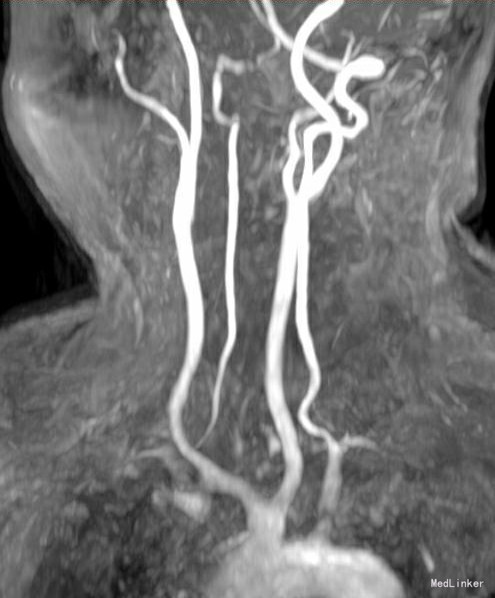

神经科查体:神清语明,步态平稳,查体合作,双瞳孔等大正圆,D=3.0mm,对光反射灵敏,双眼球各向运动充分,无眼震,无复视,额纹对称,双侧鼻唇沟对称,示齿口角不偏,伸舌居中,咽反射存在,转颈耸肩对称有力,四肢肌力Ⅴ级,肌张力正常,深感觉未见异常,右侧指鼻、轮替、跟膝胫试验略差,闭目难立征及走直线征阴性,BCR L++R++,PSR L++R++,Babinski征L-R-,颈软。余神经系统查体未见明显异常。 颅脑MRI检查,提示右侧小脑半球新发梗塞,颈椎MRI:颈3-4T2高信号。MRA提示双侧椎动脉狭窄

患者青年女性,存在双侧椎动脉狭窄及高颈段、小脑梗死,患者无一般传统动脉硬化危险因素,建议患者进一步完善风湿免疫等检查,患者拒绝,嘱患者结束妊娠后到我科继续诊治。